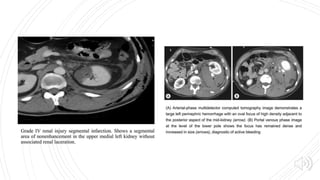

Grade I Grade II Grade III Grade IV Grade V

Include injuries to

renal parenchyma

and collecting

system as well as

vascular injuries.

Lacerations

extending deep to

involve the

collecting system

with urinary

extravasation are

included.

Delayed imaging

usually shows

urine leaking into

the perirenal

space